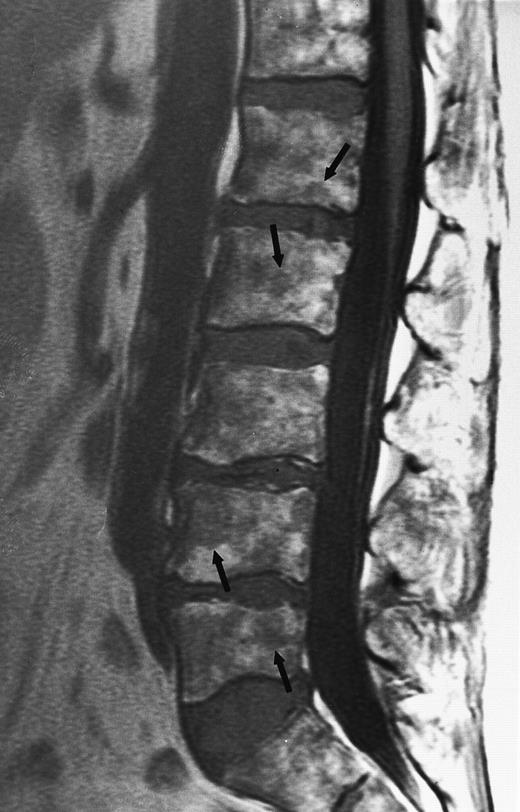

A 78-year-old woman with aplastic anemia and MR evidence of foci of hypercellular marrow. T1-weighted (500/10, TR/TE) sagittal MR image of the lumbar spine shows multiple foci of dark signal (arrows) on a background of bright aplastic marrow. On enhanced MR images (not shown), the lesions enhanced. Bone marrow biopsy showed myelodysplasia.

The detection of either focal or diffuse loss of the bright signal of the aplastic marrow, in the absence of hemosiderosis, may provide evidence for clonal disease (Fig 14). Negendak et al74 identified unexpected foci of hypercellular marrow on MR images of the spine in eight patients with a clinical diagnosis of aplastic anemia. Seven of these patients showed adjunctive evidence of myelodysplastic syndrome. Care should be taken to avoid misdiagnosing foci of regenerating hematopoietic marrow for clonal disease in patients with aplastic anemia who respond to treatment. Various MR techniques, including STIR images and contrast-enhanced images, may be used in an attempt to differentiate between the two entities.